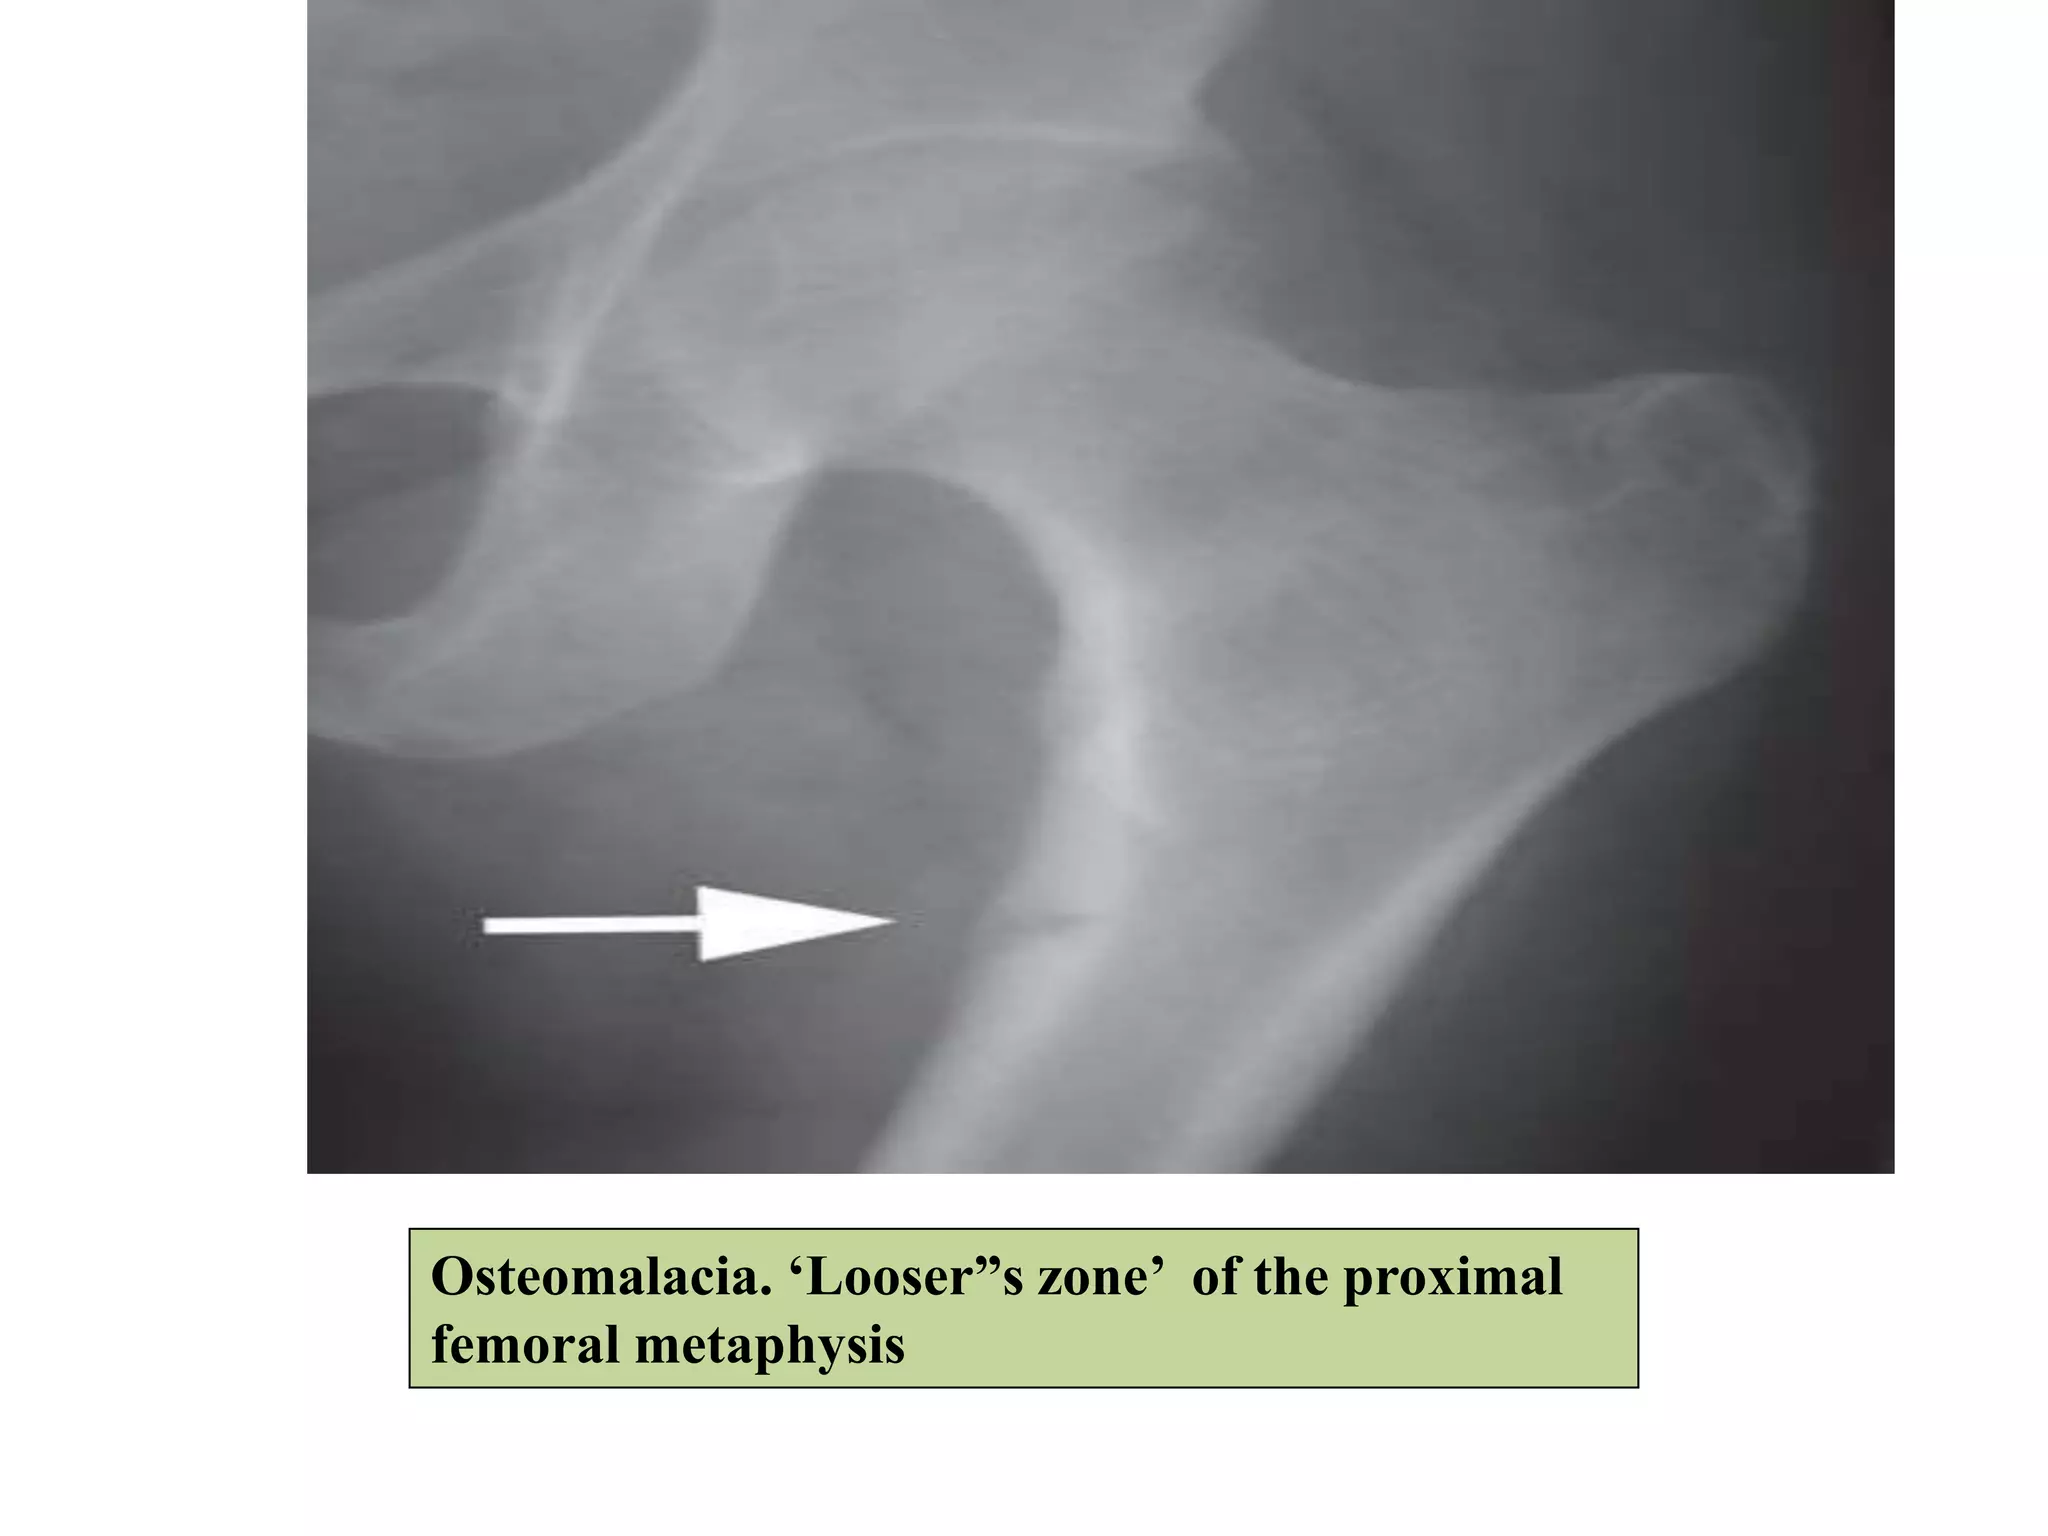

Radiological features

Common sites

-Pubic rami

-Proximal femur

-Scapula

-Lower ribs & ulna

Looser’s

Zones

Osteomalacia. ‘Looser”s zone’ of the proximal

femoral metaphysis